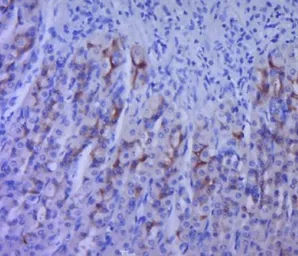

ApplicationsWB IHC-P IHC-Fr FCM

ReactivityHuman, Mouse, Rat